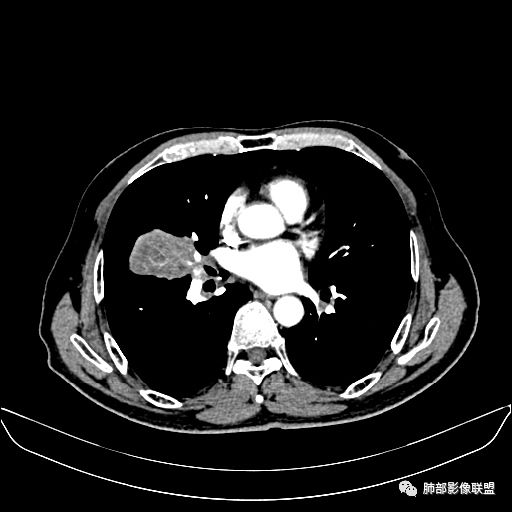

入院CT

动脉期